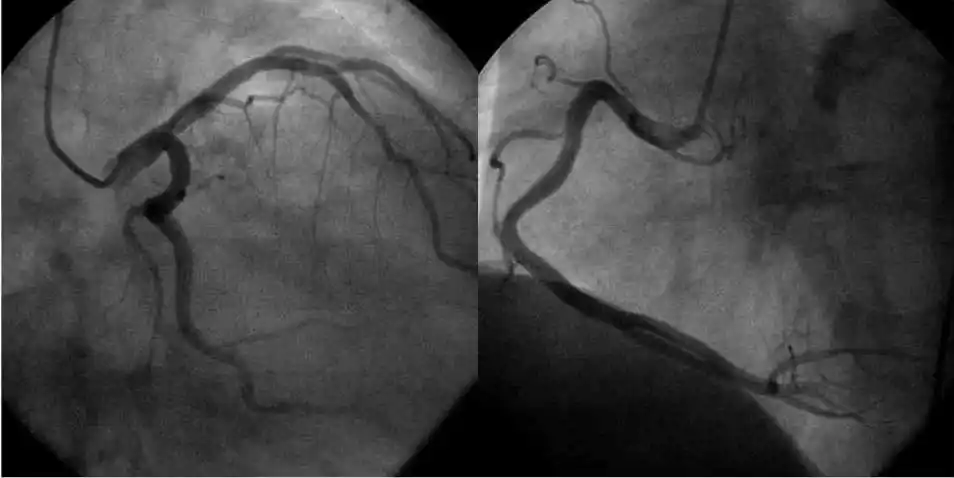

冠脉造影术在局部麻醉下进行,而血管及心脏内均无感觉神经,患者只在